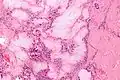

Micrograph of a gouty tophus